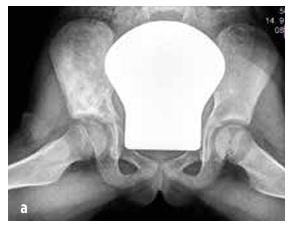

Septični artritis se pojavi v 50 % primerov v dveh letih starosti, v 75 % primerov pa prizadene sklepe spodnjih okončin (koleno > kolk > gleženj) (glej sliko 4). Osteomielitis je najpogosteje lokaliziran v metafizi.

Pri otrocih z nenadnim pojavom zvišane telesne temperature, nepojasnjenim šepanjem in/ali nenormalno držo okončin, zavračanjem uporabe okončine, omejenim obsegom gibanja, bolečino v mišično-skeletnem sistemu ± lokalizirano občutljivostjo sklepa ali kosti ter oteklino z rdečico (glej sliko 4) upoštevamo okužbo kosti ali sklepa. POZOR: majhni otroci ne morejo natančno lokalizirati bolečine (npr. bolečina se prenaša iz kolka v koleno).

Slika št. 4

Klinični izvidi pri septičnem artritisu